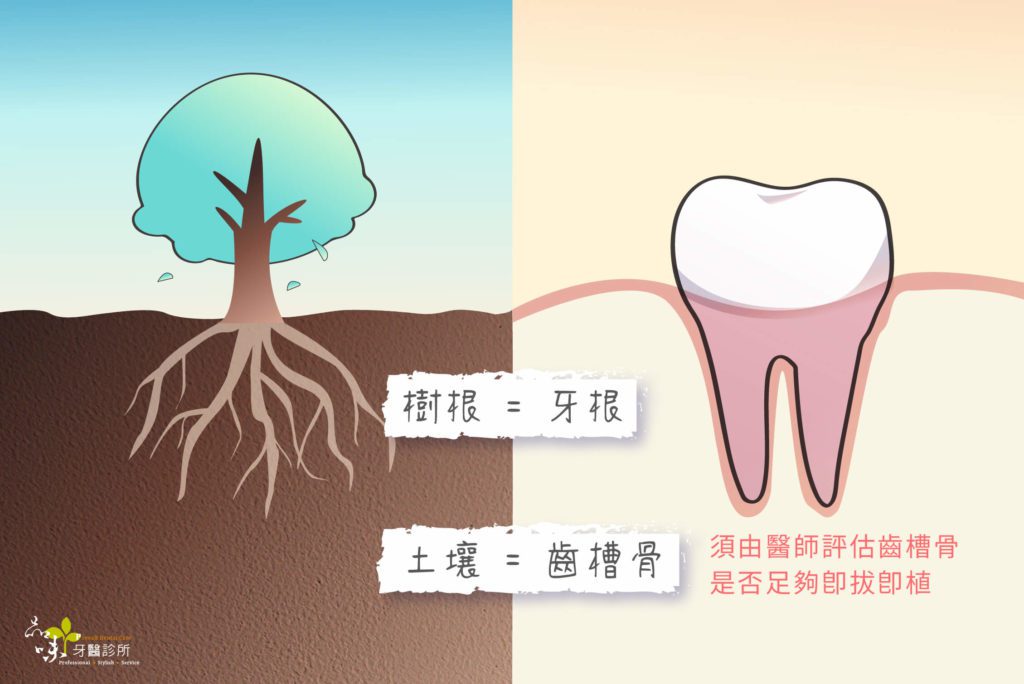

當下拔牙後,可以立即植牙嗎?還是需要再多等半年?其實齒槽骨條件合適的患者,經過 X 光與 CT 電腦斷層評估後可以考慮做即拔即植的治療。除了能縮短治療期程外,也可以少挨一次刀,不必再另外多鑽一個洞,是較快能微創重建缺牙的其中一個方式。

其實不然,因為不是每位患者都適合這項手術。即拔即植屬於難度較高的手術項目,且患者的牙齒與齒槽骨必須符合特定條件才行。若有牙根發炎嚴重、齒槽骨缺損廣泛、齒槽骨量不足、植體初期穩定度 (Primary stability) 不足⋯⋯等因素,將無法施行即拔即植手術。

由於每個人的牙齒、骨頭狀況皆不同,因此,拔牙前一定要先給專業醫師評估過後,才知道自己適不適合做這項術式。